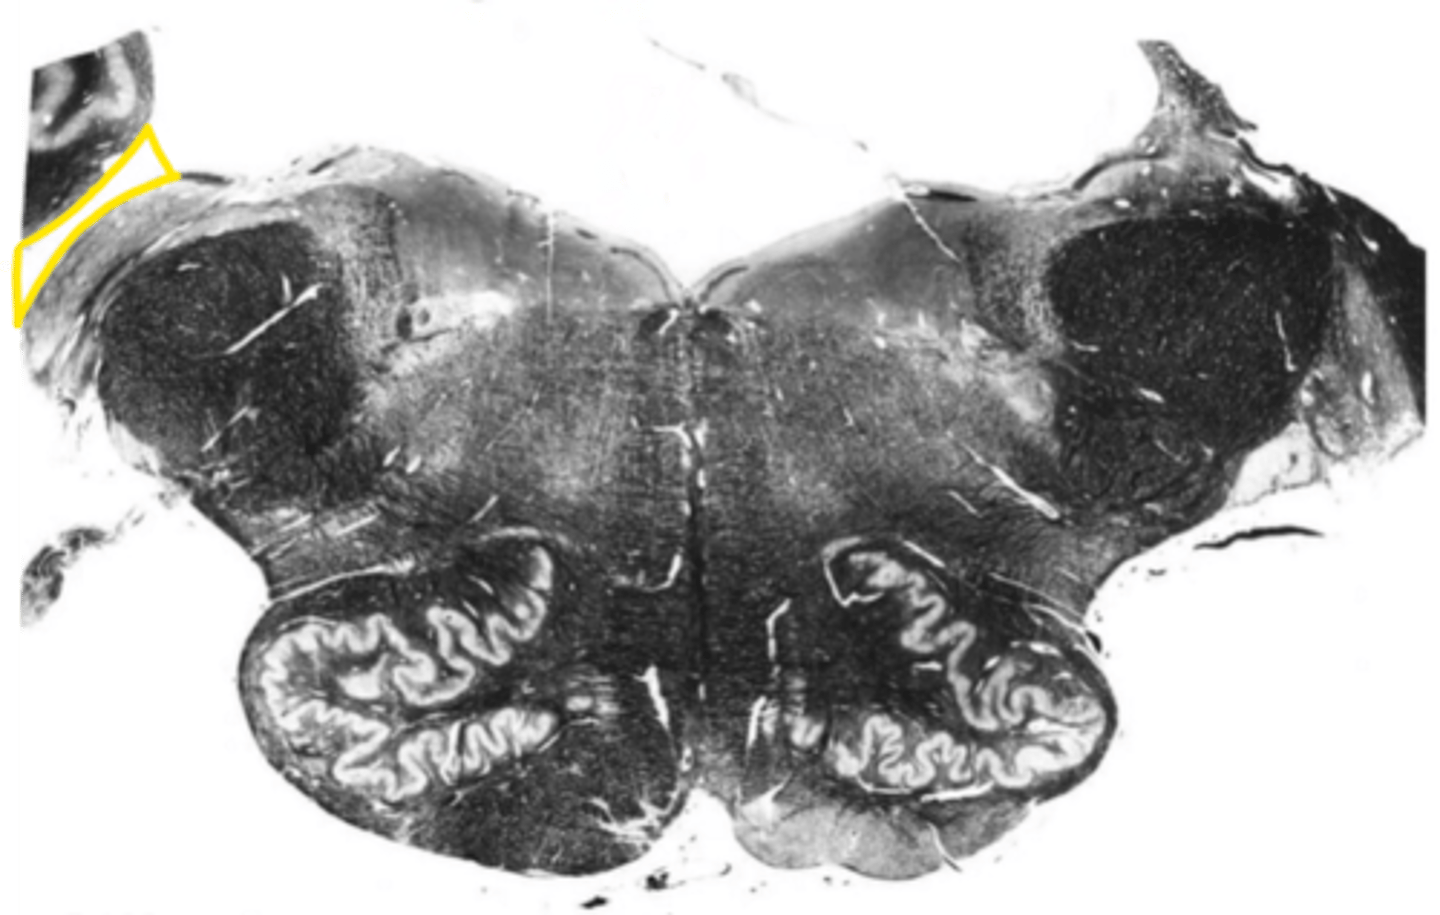

fourth ventricle

ID the space

open medulla

ID the area

superior cerebellar peduncles

ID the structure

inferior cerebellar peduncles